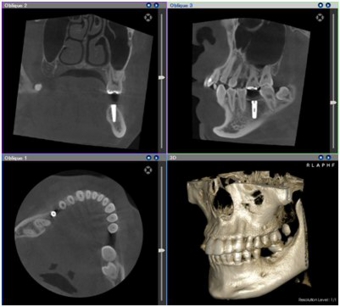

診査と診断(カウンセリング)

患者さんの全身状態の問診と口腔内の状態の診査を行います。

あごの骨の量と質を記録するため、口の中の型を取り、レントゲン・CT撮影を行います。

これらのデータを用いて、一人ひとりの患者さんに適した治療計画を立案します。

*保存不可能な歯を抜いてからインプラントをする場合、抜いた後、骨が治癒するまでの期間(約6か月)待たなければなりません。その後、治癒した部分にインプラント治療が可能か、再度CTや模型にて精密な診査・診断が必要です。